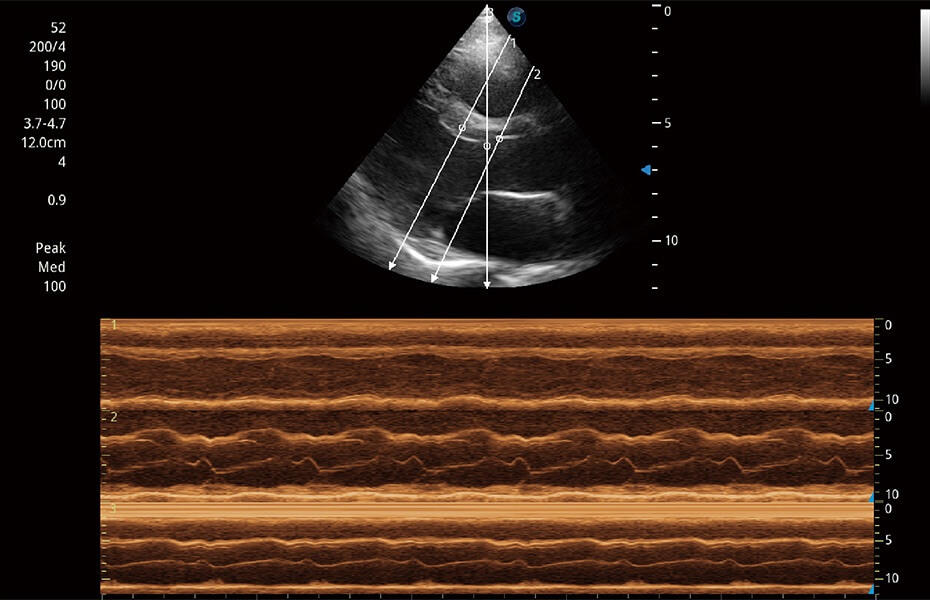

• AMM 解剖M型

通過(guò)360度任意調(diào)節(jié)3條M型取樣線(xiàn),在同一心動(dòng)周期上觀察心臟不同位置的運(yùn)動(dòng)曲線(xiàn),得到準(zhǔn)確的心功能測(cè)量數(shù)據(jù),有效評(píng)估心肌運(yùn)動(dòng)及左心室功能。

(犬)乳頭肌短軸

(貓)二尖瓣M型